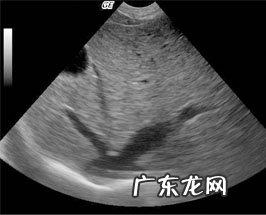

腹腔彩超检查

腹腔彩超检查:腹腔彩超检查发觉肝部扩大 , 肝本质回音匀称 , 内未见异常回音疾病 , 肝毛细血管增大增粗 , 这种转变是因为心力衰竭造成回心力量降低 , 肝部血肿而致 。腹部内丰富性无回音影象 , 提醒存有很多腹腔积水 。